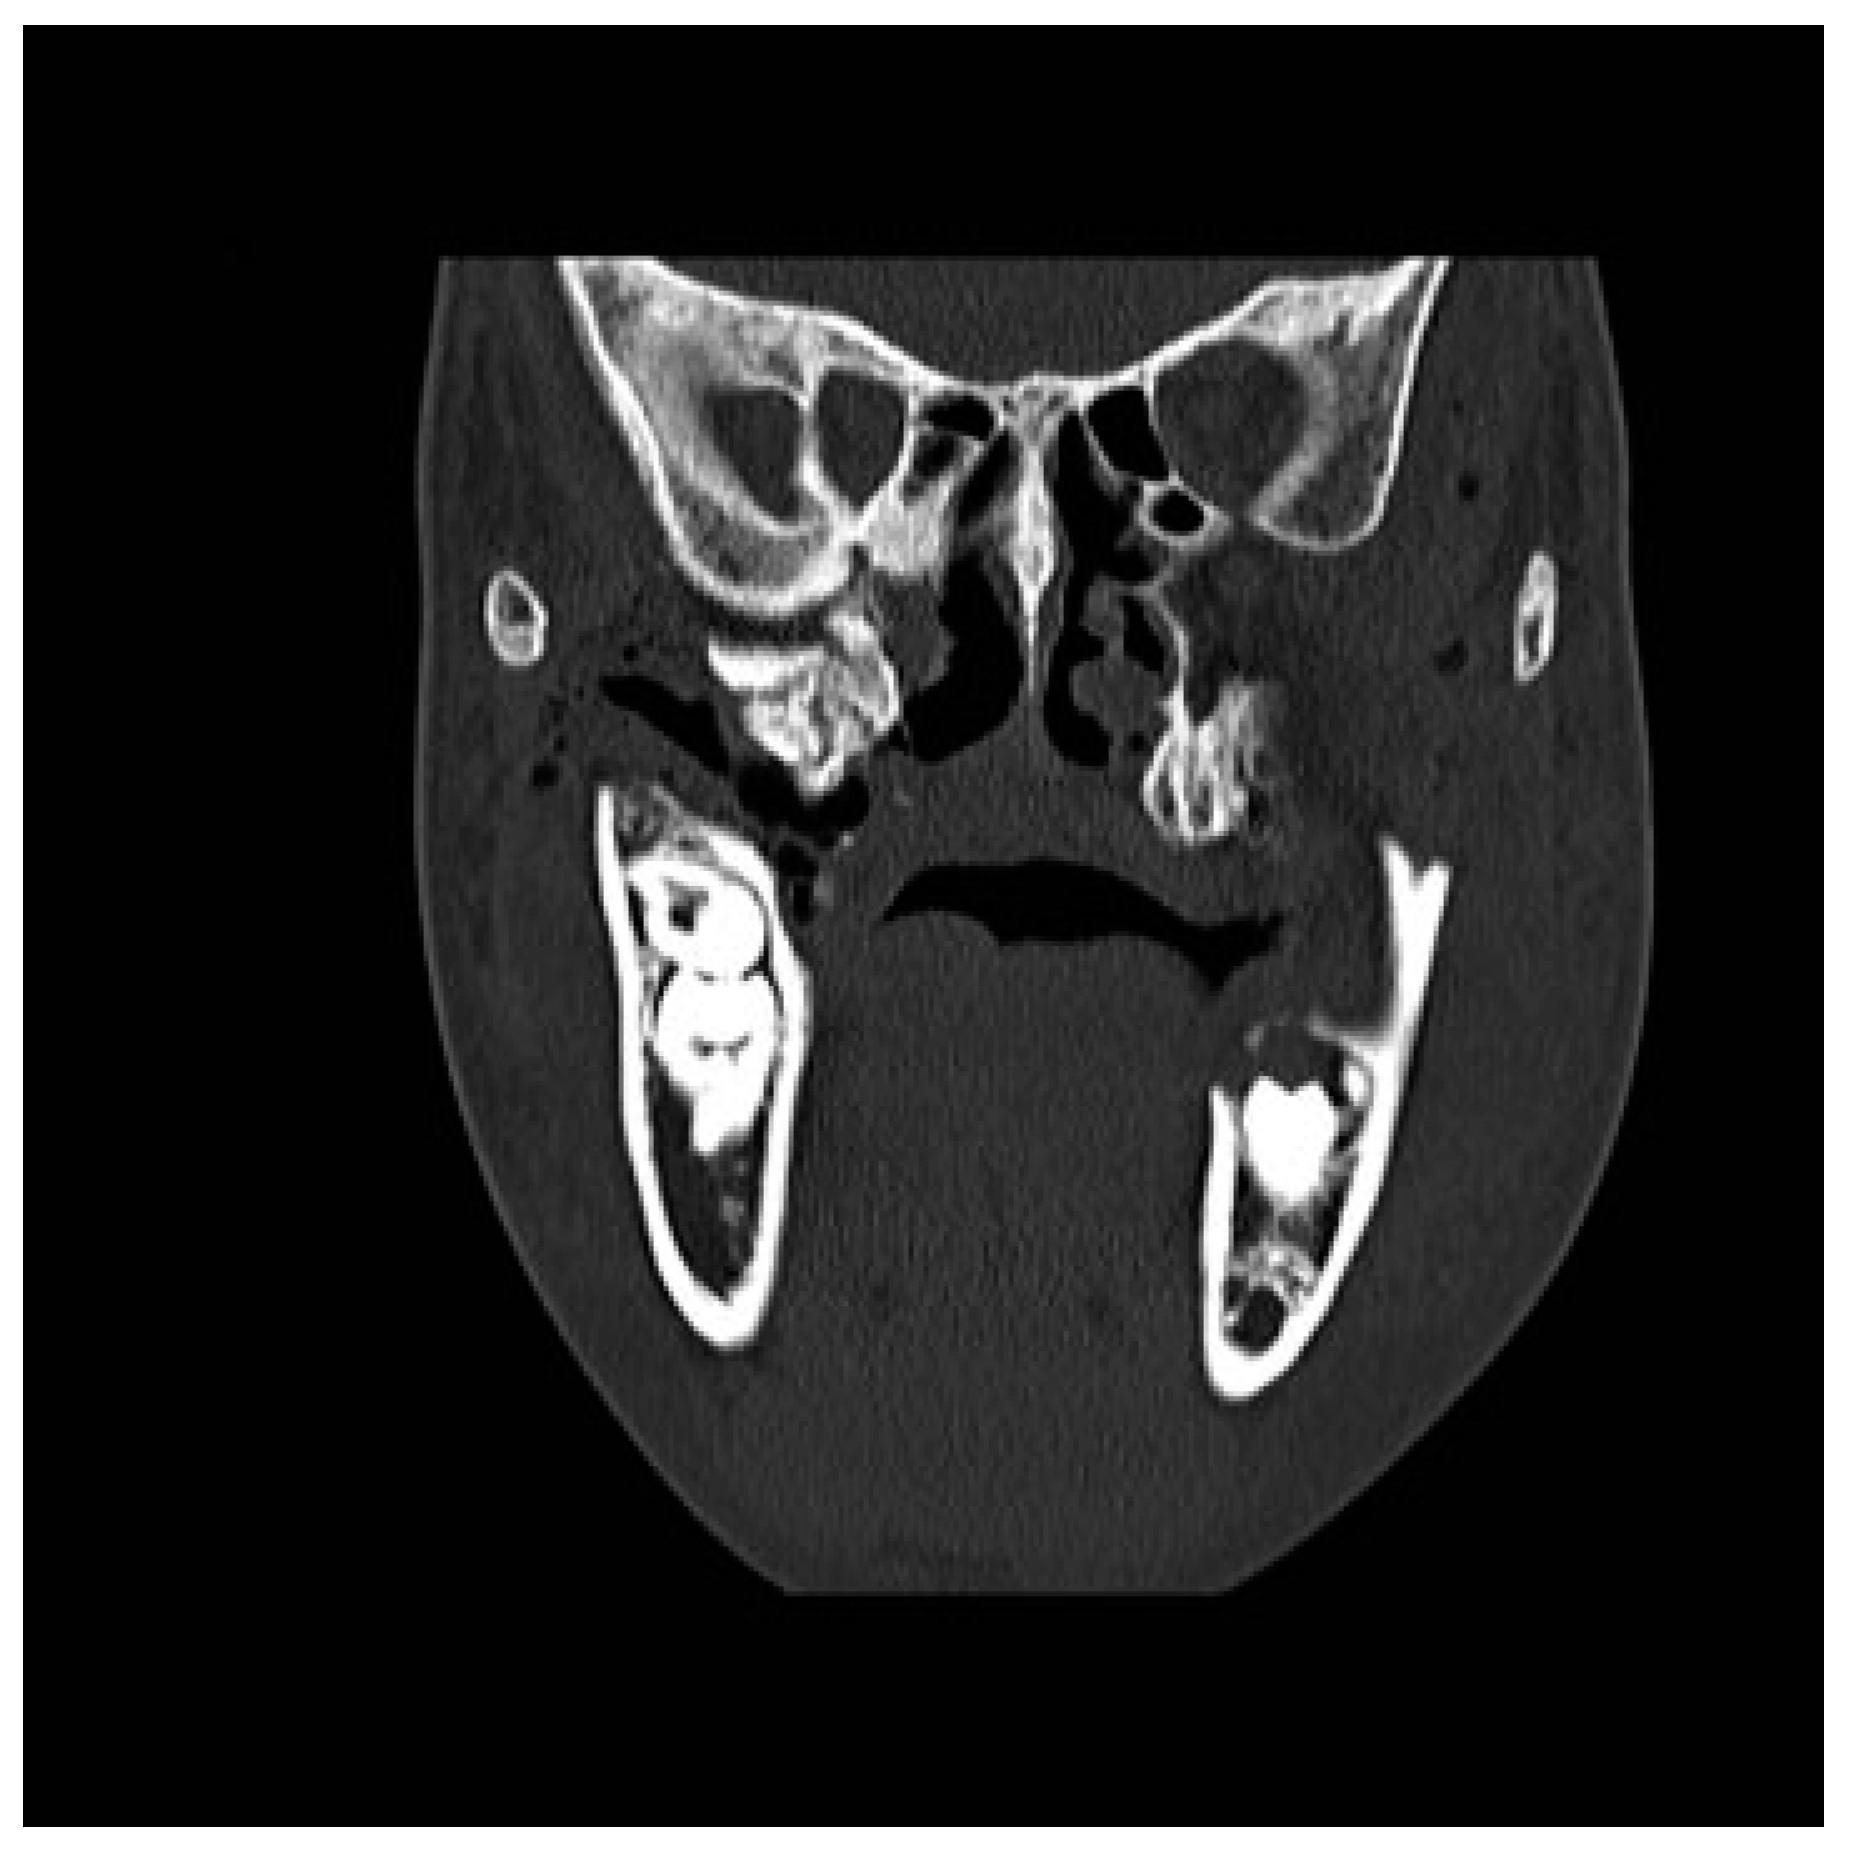

Figure 1. Preoperative CT scan. Axial view: right maxillomandibular fusion.

A CT scan of the head with 3D reconstruction (Figure 1, Figure 2, Figure 3, Figure 4 and Figure 5) confirmed a maxillomandibular fusion associated with a cleft palate, agenesis of the right turbinate, and right hemifacial microsomia (Laster type 2b syngnathia). Both temporomandibular joints (TMJs) were normal and showed no bony ankylosis (fibrous ankylosis could not be excluded with the given data).

Figure 3. Preoperative CT scan. Coronal view: right maxillomandibular fusion.